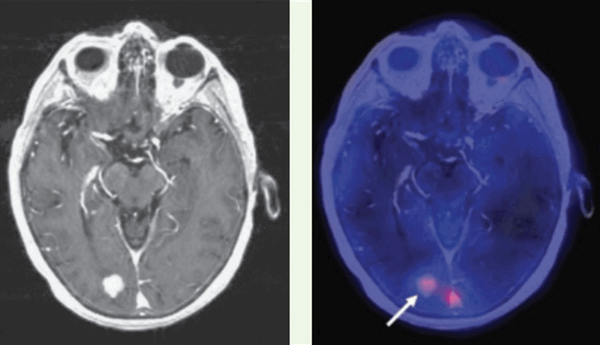

КТ-ПРИЗНАКИ МЕТАСТАЗОВ В ГОЛОВНОЙ МОЗГ

Как выглядят метастазы в головной мозг на компьютерной томографии (КТ)? Практически во всех случаях выявляется единичное (реже) либо множественные (чаще) объемные образования, которые отвечают следующим параметрам:

- Форма неправильная или сферическая

- Структура неоднородная, в центре очага может обнаруживаться область низкой плотности, обусловленная некрозом и распадом центральной части опухоли. По периферии — более плотный «ободок», который отражает активную часть опухоли, имеющую кровеносные сосуды и обладающую способностью к росту. Этот «ободок» окружен зоной низкой плотности, отражающей отек ткани мозга. Ширина данной зоны может быть различной — от нескольких мм до нескольких десятков см. Относительно однородная структура без наличия участка низкой плотности в центре и без перифокального отека. Такая структура метастаза свидетельствует о его относительной «доброкачественности»

- Отношение к прилежащим мозговым структурам. Очаги могут оказывать объемное воздействие различной степени выраженности на прилежащие отделы мозга, вызывая их смещение. Например, объемное образование в височной доле чаще всего приводит к выбуханию гиппокампа под намет мозжечка (височно-тенториальная дислокация), объемное образование мозжечка может воздействовать на мозговой ствол, приводя к его сдавлению, и т. д. Смерть при метастазах в мозг может наступить в результате сдавления мозгового ствола и нарушения дыхания и сердечной деятельности. В зависимости от локализации, вторичные очаги могут приводить к сдавлению церебральной ликворной системы, приводя к развитию окклюзионной гидроцефалии (резкому расширению центральных ликворных пространств на фоне повышения внутримозгового давления при окклюзии путей оттока ликвора из полости черепа)

- Параметры контрастного усиления. Типичные вторичные опухоли в головном мозге увеличивают свою плотность в периферических отделах при внутривенном введении контраста, принимая вид «кольца», «полукольца», «спирали». Гораздо реже наблюдается равномерное контрастное усиление очага. Обычно центральная зона опухоли не усиливается, как и область перифокального отека.

Метастазы головного мозга, фото. На КТ с контрастным усилением у пожилой пациентки (в верхнем ряду слева) с жалобами на головные боли выявлены множественные объемные образования в левом полушарии мозга, интенсивно накапливающие контрастное вещество. Образования имеют характерную форму в виде «кольца». На изображениях в нижнем ряду и вверху справа определяются множественные очаги в головном мозге: отчетливо видны округлые образования с более плотным «ободком» по периферии, располагающиеся в левой теменной доле.